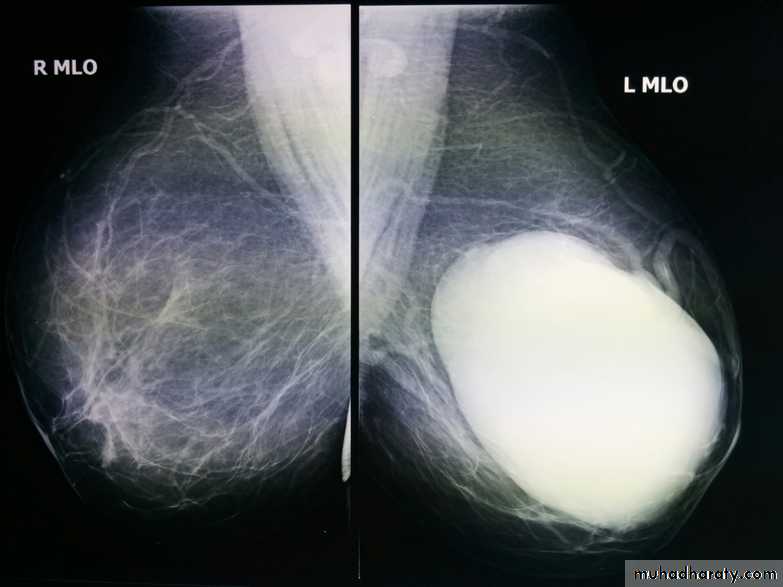

ILC is more often multicentric and bilateral (10-15%). Therefore imaging evaluation of the contralateral breast is crucial. There can be very subtle changes such as progressive shrinkage or enlargement or reduced compressibility of the involved breast. Imaging often underestimates the disease.

Mammography